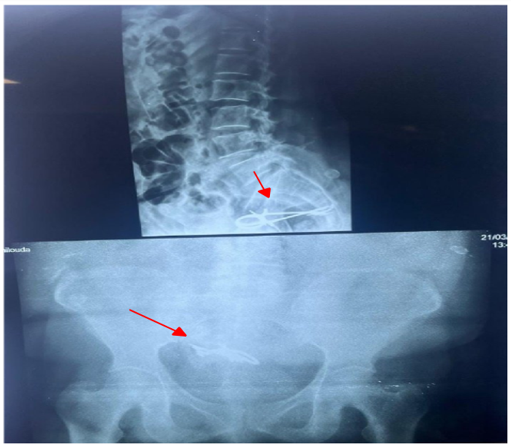

Preoperative pelvic X-rays (frontal and lateral) were performed to identify and localize the metallic foreign body. An exploratory laparotomy was done under general anesthesia with a Pfannenstiel transverse incision. Palpation revealed a metallic foreign body at the bladder dome. Urologists intervened and extracted half of the instrument intravesically. Exploration revealed a fistulous tract between the bladder and meso-sigmoid. Another fragment of the clamp was removed, followed by fistula closure and placement of two ureteral stents.

Figure 2: Preoperative pelvic X-ray localizing the metallic foreign body